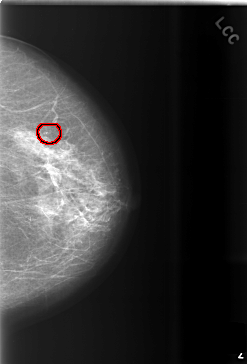

FILE: C_0508_1.LEFT_CC.OVERLAY

TOTAL_ABNORMALITIES 1

ABNORMALITY 1

LESION_TYPE CALCIFICATION TYPE PUNCTATE DISTRIBUTION CLUSTERED

ASSESSMENT 3

SUBTLETY 4

PATHOLOGY BENIGN

TOTAL_OUTLINES 1

BOUNDARY